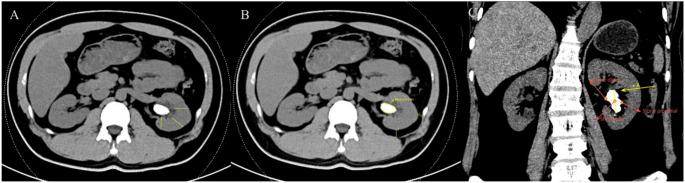

This study aimed to identify preoperative risk factors for systemic inflammatory response syndrome (SIRS) in patients with metabolic syndrome (MetS) undergoing percutaneous nephrolithotomy (PCNL) and to develop a predictive nomogram for individualized risk stratification. A retrospective analysis was conducted on 245 MetS patients who underwent PCNL between January 2021 and December 2024, among whom 27.8% developed postoperative SIRS. Patients were randomly assigned to training and validation cohorts in a 7:3 ratio. Least absolute shrinkage and selection operator (LASSO) regression was initially applied to select candidate predictors, followed by univariate and multivariate logistic regression analyses to identify independent risk factors. A nomogram was subsequently constructed based on the significant variables and evaluated using receiver operating characteristic (ROC) curves, calibration plots, and decision curve analysis (DCA). Multivariate analysis identified five independent predictors of postoperative SIRS: higher standard deviation of stone density, reduced renal parenchymal thickness, increased lateral and posterior perirenal fat thicknesses, and the presence of staghorn calculi (P < 0.05). The nomogram demonstrated good discriminative ability, with an area under the ROC curve (AUC) of 0.888 (95% CI: 0.834-0.942) in the training cohort and 0.882 (95% CI: 0.802-0.962) in the validation cohort. The calibration curve and the Hosmer-Lemeshow test (P = 0.1485) indicated good model calibration and fit. DCA further confirmed the clinical utility of the model. This nomogram offers a reliable preoperative tool for SIRS risk stratification in MetS patients undergoing PCNL, aiding early intervention and personalized perioperative management.

本研究旨在确定接受经皮肾镜取石术(PCNL)的代谢综合征(MetS)患者发生全身炎症反应综合征(SIRS)的术前危险因素,并制定个性化风险分层的预测列线图。对2021年1月至2024年12月期间接受PCNL的245例MetS患者进行回顾性分析,其中27.8%发生术后SIRS。患者按7:3的比例随机分为训练队列和验证队列。最初应用最小绝对收缩和选择算子(LASSO)回归来选择候选预测因素,随后进行单变量和多变量逻辑回归分析以确定独立危险因素。随后基于显著变量构建列线图,并使用受试者工作特征(ROC)曲线、校准图和决策曲线分析(DCA)进行评估。多变量分析确定了术后SIRS的五个独立预测因素:结石密度标准差较高、肾实质厚度降低、肾周外侧和后侧脂肪厚度增加以及鹿角形结石的存在(P<0.05)。列线图显示出良好的判别能力,训练队列中的ROC曲线下面积(AUC)为0.888(95%CI:0.834-0.942),验证队列中的AUC为0.882(95%CI:0.802-0.962)。校准曲线和Hosmer-Lemeshow检验(P=0.1485)表明模型校准良好且拟合度高。DCA进一步证实了该模型的临床实用性。该列线图为接受PCNL的MetS患者的SIRS风险分层提供了一种可靠的术前工具,有助于早期干预和个性化围手术期管理。